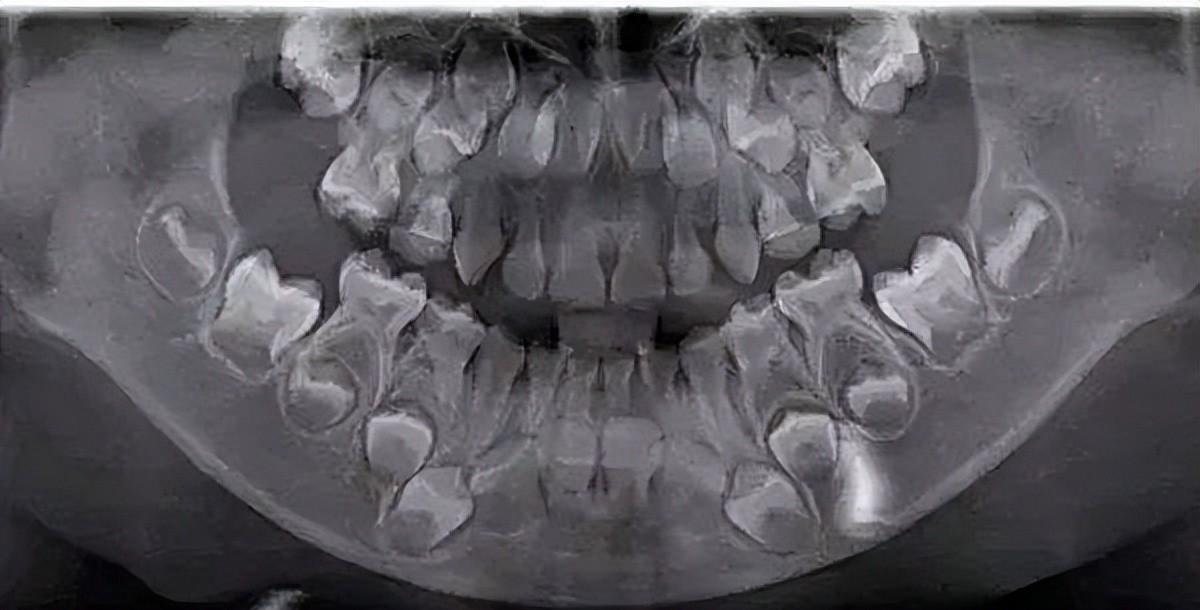

一般情况下,健康的牙齿表现为牙冠完整,表面是乳白色,由半透明的釉质构成,表面没有虫牙和其他的牙体组织缺损,牙齿通过牙根部与牙槽骨相连,也就是长在上下颌骨内。

因此,如果你的牙齿表面出现了黑线,黑线等情况,并且在刷牙、漱口后依旧无法清理掉的话,那么你很可能患有龋齿。

一般情况下,牙齿龋坏不严重的话,只需要进行去腐后使用树脂/玻璃离子/嵌体等材料进行修补即可;如果龋坏严重伤及牙神经,那么就要进行根管治疗,这时候价钱一般比普通不要要高出5、6倍。